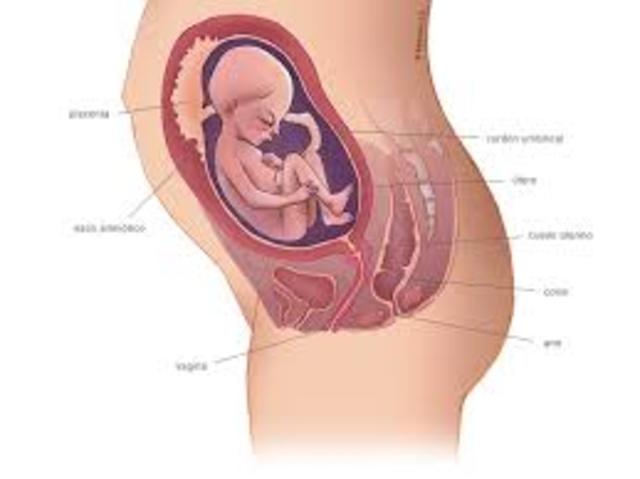

El feto a estas semanas empieza a ubicarse en la posición definitiva que tendrá al nacer, que en la mayoría de los casos es con la cabeza hacia abajo a pesar de que puede cambiarla hasta el momento del parto. En algunos caso los fetos se posicionan de nalgas o situación transversa debido a una falta de movilidad por un cordón umbilical corto o enredado en el feto, por la forma del útero materno o simplemente porque se siento mucho mejor en esa posición.